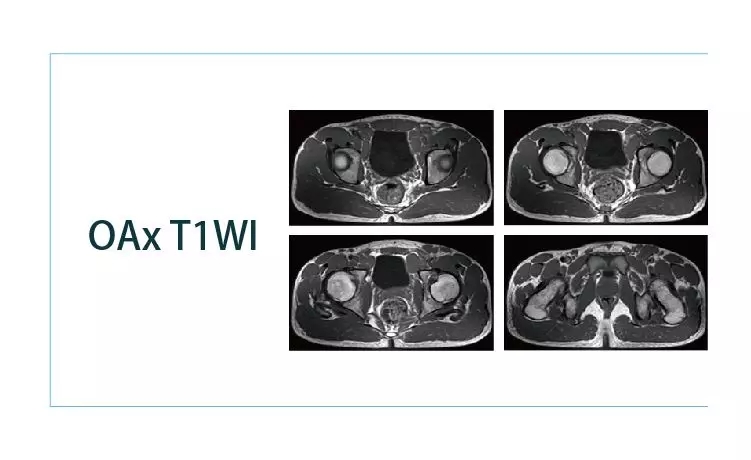

【朗润影像档案】20190405磁共振影像病例结果讨论